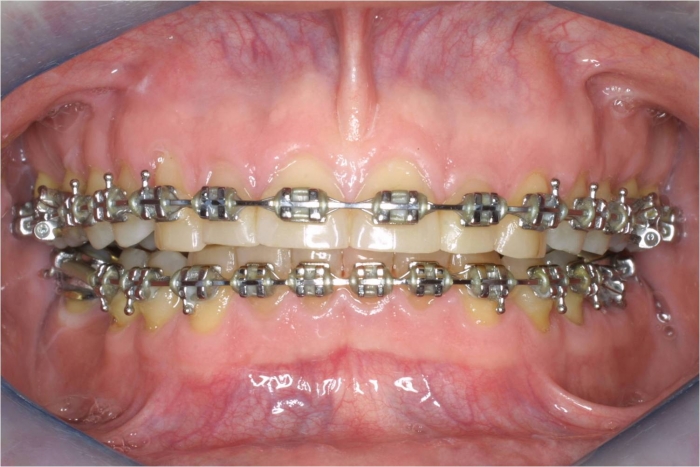

Mordida inicial